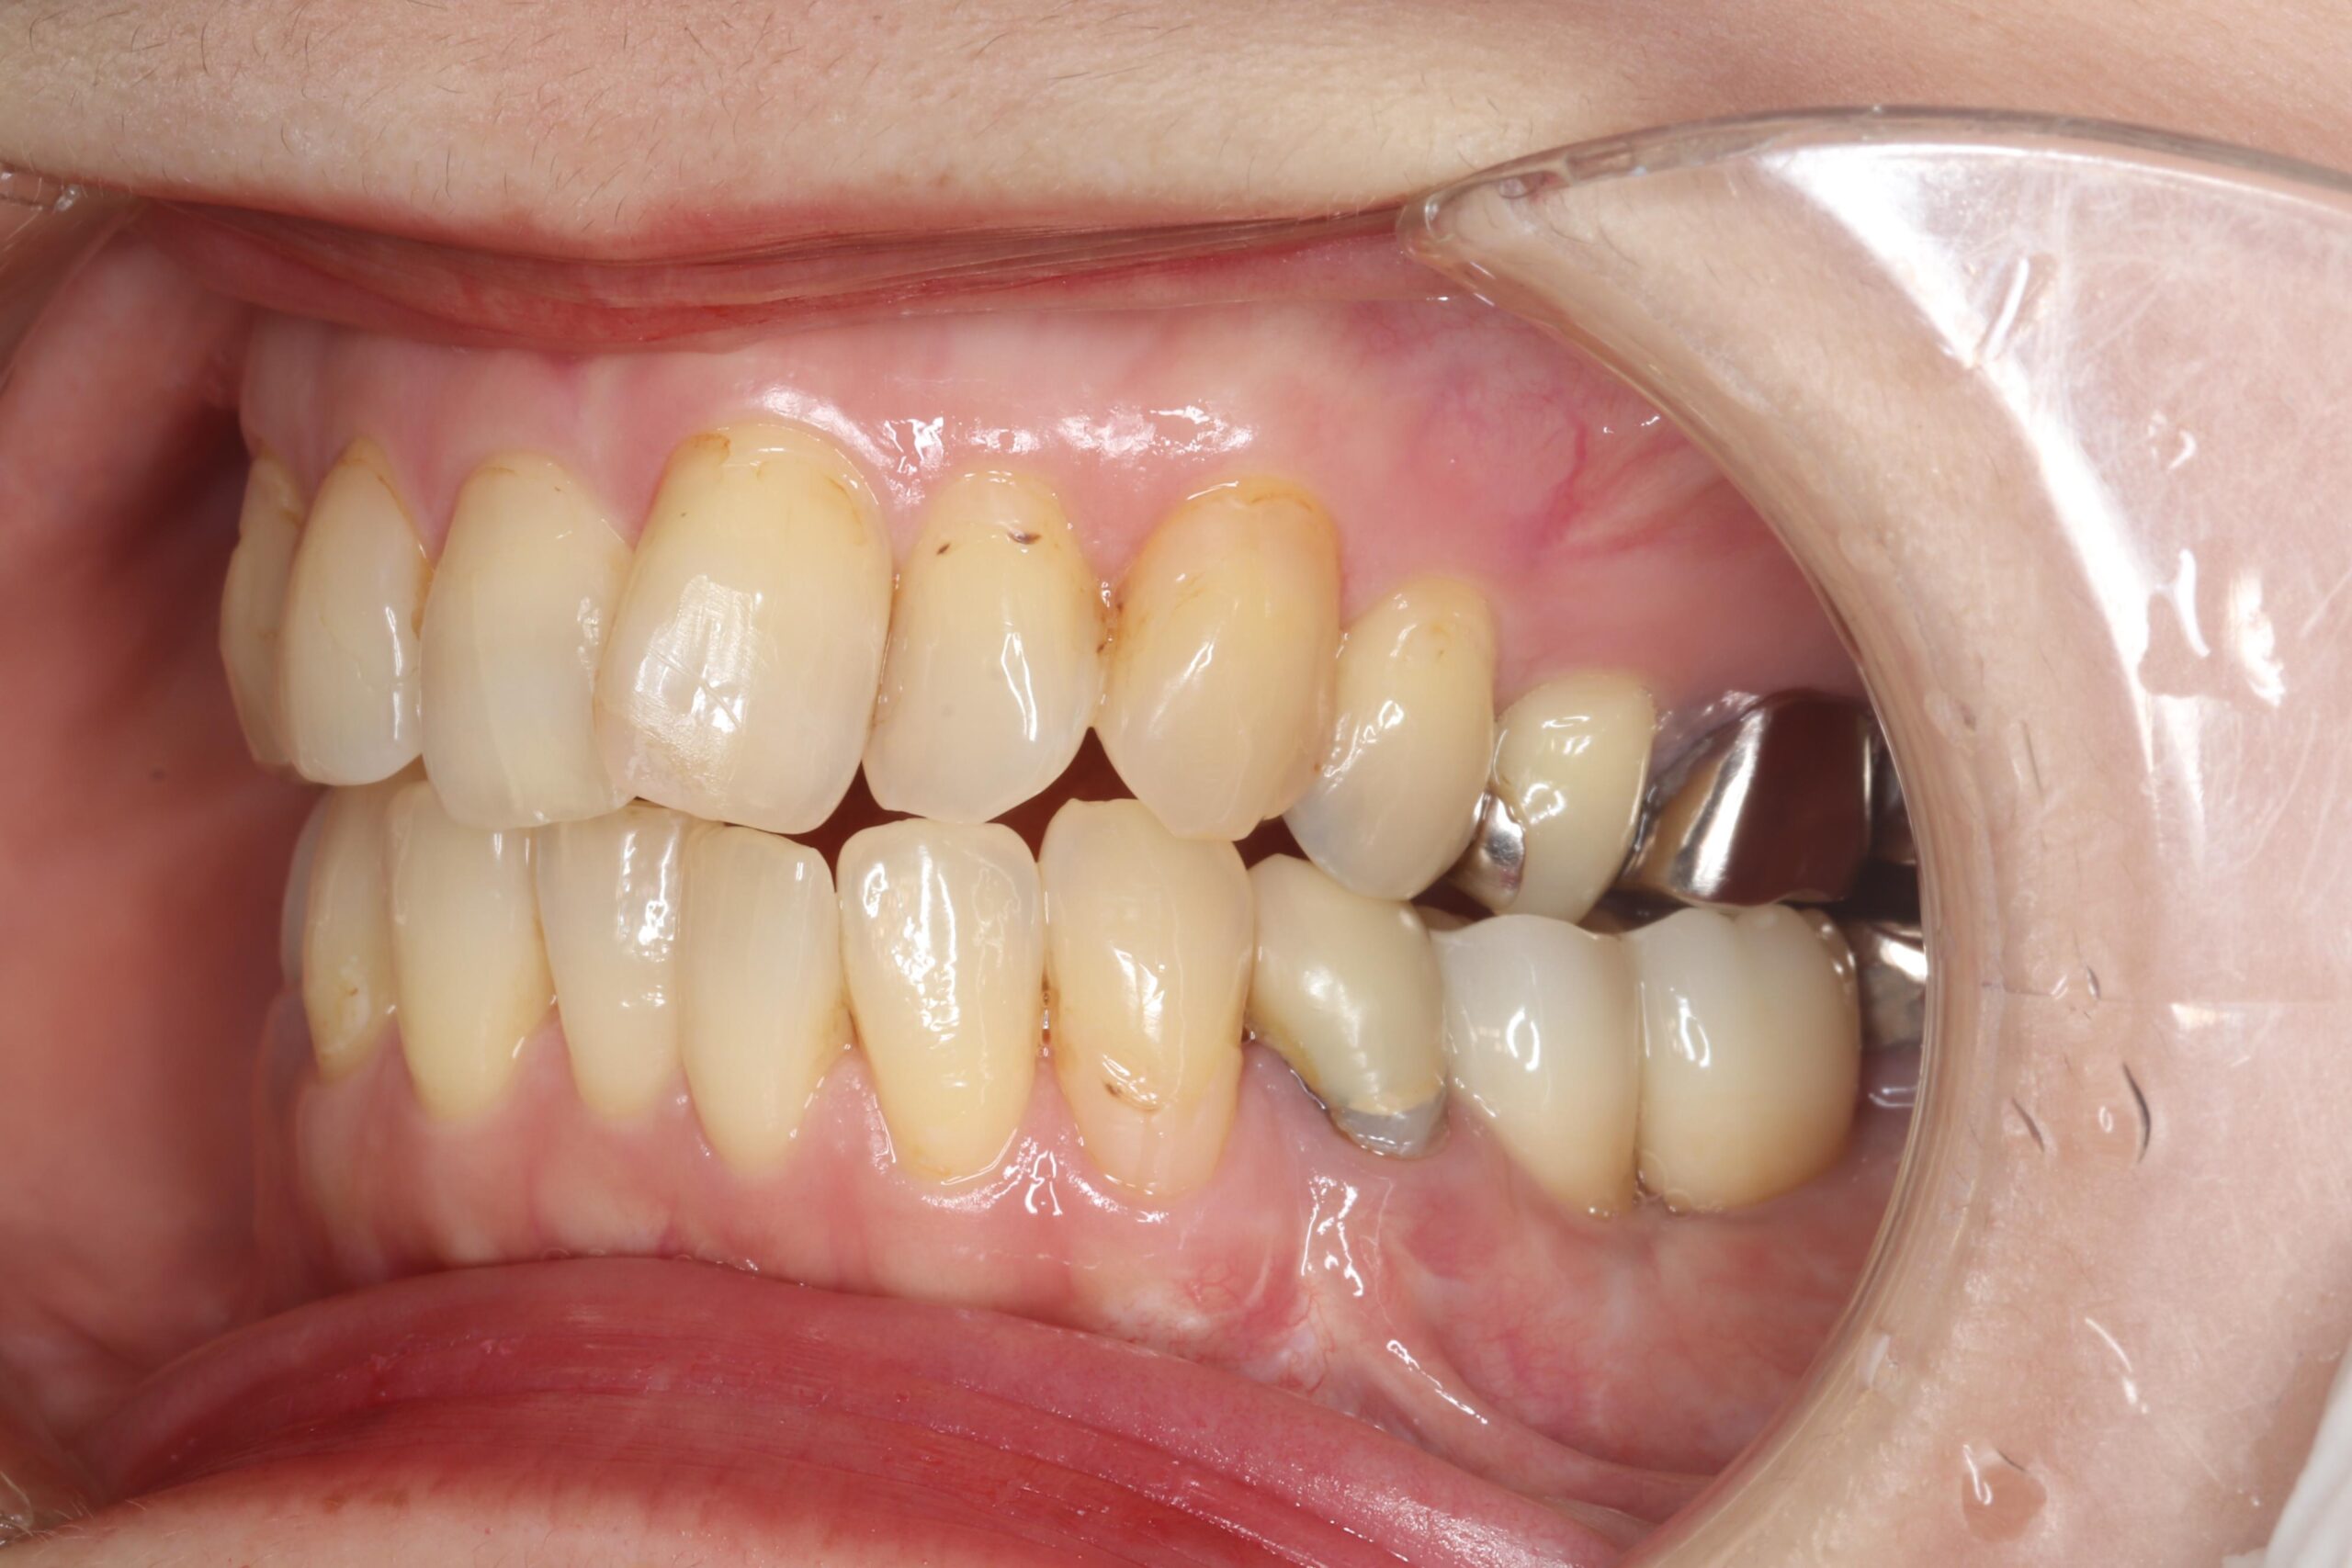

症例02

70代 男性 咬み合わせが強く多くの歯がすぐに壊れる

| 主訴 | 咬み合わせが強く、治療をしてもつくった歯がすぐに壊れる。 他院ではインプラントをいれることも難しいため、断られた。 |

|---|---|

| 年代・性別 | 70代 男性 |

| 治療部位 | 下顎両側 5,6 上顎右側 4 6のインプラントブリッジ ※全顎的に、臨床的歯冠長延長術(クラウンレングスニング)を行い、セラミッククラウンの強度を増しています。 |

| 治療費用 | インプラント 440,000円×6本 |

| 手術回数 | 下顎1回 上顎1回 |

| 治療期間 | 下顎6ヶ月 上顎6ヶ月 |

| 手術時間 | 下顎90分 上顎60分 |

| 治療回数 | 下顎1回 上顎1回 |